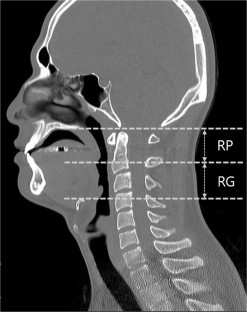

A total of 118 subjects with sleep breathing disorders were analyzed. Participants underwent upper airway CT scans in the supine and lateral decubitus positions (right and left). They were divided into non-obstructive sleep apnea (n = 28) and obstructive sleep apnea (n = 90) groups. We measured the minimal cross-sectional area of the retropalatal/retroglossal spaces and compared the differences of those two spaces in the supine and lateral positions. CT was performed while patients were awake.

The minimal cross-sectional area in the OSA group was significantly smaller than non-OSA group in both supine (median[interquartile range], 8.3[0.0–25.1] vs 22.2[1.0–39.6]; P = 0.018) and lateral decubitus positions (5.2[0.0–16.9] vs 21.3[6.1–38.4]; P = 0.002). As the body position of OSA patients shifted from supine to lateral, the retroglossal space increased significantly (67.3[25.1–116.3] vs 93.3[43.4–160.1]; P < 0.001). However, there was no significant difference in the retropalatal space between the supine and lateral decubitus positions.

Positional change from the supine to lateral decubitus position expands the upper airway lumen, especially the retroglossal space. Positional OSA may be related to anatomical change of the upper airway lumen based on body position.